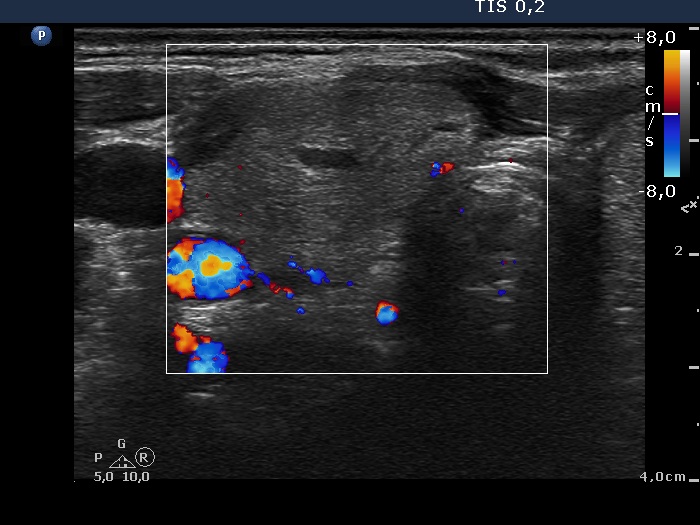

Ethanol sclerotherapy: non-toxic solid nodules - Case 5

Twelve years after the therapy (ultrasonographic picture 3)

Right lobe, horizontal section, color Doppler mode. The vascularization is scanty.